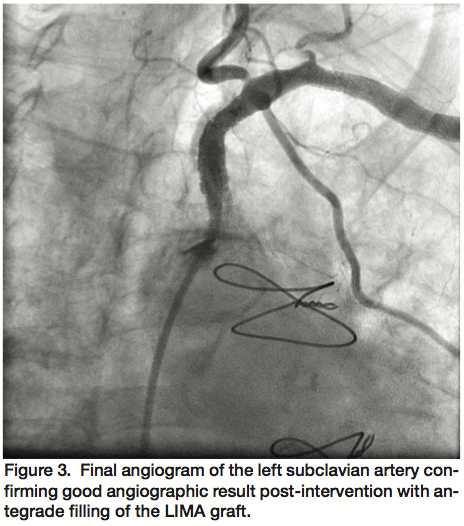

Access was obtained in the left brachial artery and a 25 cm 6 Fr sheath advanced into the subclavian artery for initial angiography, which confirmed a long occlusion of the proximal left subclavian artery (Figure 1) and reversal of flow in the LIMA as well as the left vertebral artery. We attempted to cross the occlusion with a Crosser high-frequency ablation catheter (FlowCardia Inc.), albeit unsuccessfully. Next, a 0.018-inch Astato 30 gm wire (Asahi Intecc) was introduced for a prolonged attempt at recanalization. However, the distal exit point of the subclavian into the aorta was difficult to delineate. For this reason, access was obtained in the right femoral artery and a 6 Fr internal mammary catheter advanced to the ostium of the left subclavian in an attempt at crossing the occlusion from an antegrade approach using another Astato 30 gm wire without success. Ultimately after prolonged manipulation of both Astato wires from retrograde and antegrade approaches, the wire from the brachial access was successful in crossing the occlusion into the ascending aorta (Figure 2). After aggressive balloon angioplasty, a 5 x 19 mm Express stent (Boston Scientific) was deployed in the ostial segment of the subclavian artery followed by a 5 x 15 mm Express stent in an overlapping fashion with care not to jail the LIMA graft, and these stents post-dilated using a 6 x 20 mm Sterling balloon (Boston Scientific). Final angiography performed through the internal mammary catheter revealed significantly improved angiographic result with restoration of antegrade flow through the LIMA (Figure 3).